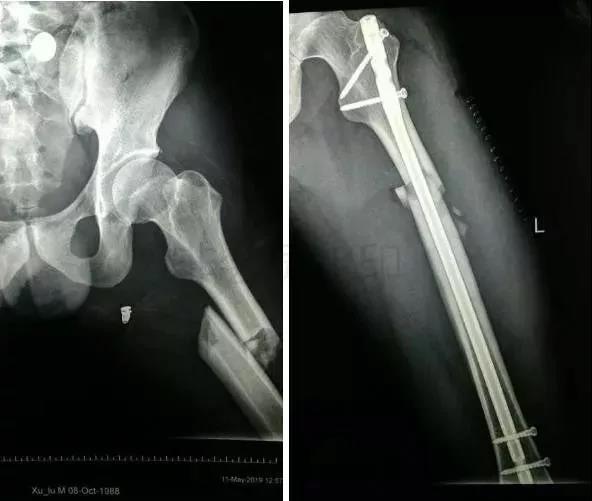

1)股骨近端(股骨头,颈,转子部位)

- <65岁,内固定;>65岁,关节置换。

- 患者全身情况稳定,应早期内固定。

- 内固定方式很多,如DHS,pfna等。

2)股骨干骨折

- 可以急诊做,也可以根据情况限期做。

- 多发伤,髓内钉,可能发生脂肪栓塞-肺栓。